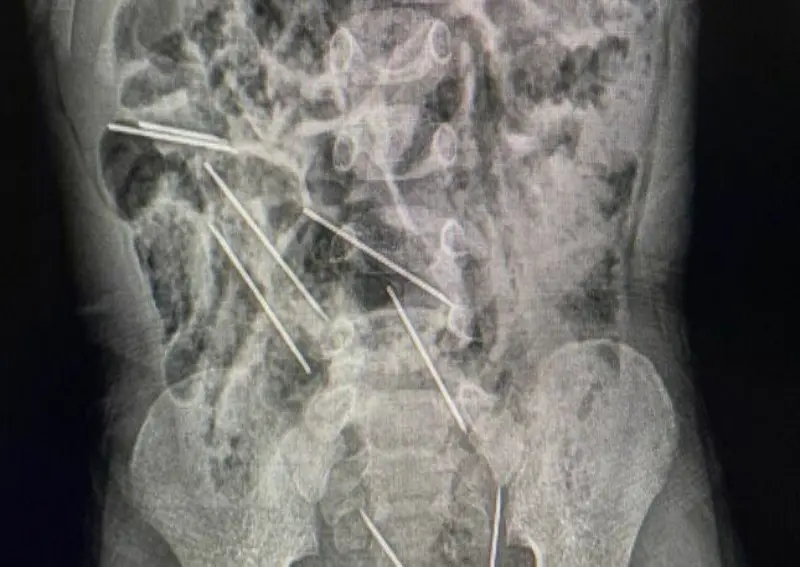

أنقذ أطباء في شمال شرقي بيرو حياة طفل، عمره عامان، بعد أن ابتلع 8 إبر حقن وهو يلعب.

وقال الطبيب إفراين سالاسار: “عندما كنا في غرفة العمليات وفتحنا بطنه وجدنا تلك القطع المعدنية، وأدركنا أنها كانت في الحقيقة إبراً”.

وذكرت وسائل إعلام محلية أن الإبر كانت من تلك التي تستخدم لتطعيم حيوانات بمزرعة تعمل فيها والدة الطفل.

ويعيش الطفل، الذي لم يتم الكشف عن اسمه، في منطقة تاراتوبو الزراعية على بعد حوالي 622 كيلومتراً من العاصمة ليما.

وقالت والدته “ربما ابتلعها عندما كان يلعب هناك”.

وذكرت وسائل الإعلام المحلية أن حياته ليست في خطر بعد الجراحة.